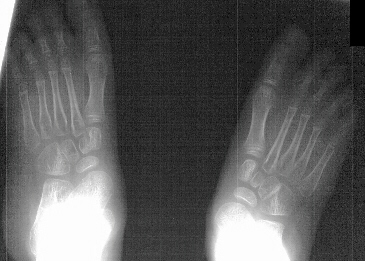

A six year old female followed for spastic quadriplegic cerebral palsy presented with increasing difficulty with ambulation secondary to bilateral hamstring tightness and progressive planovalgus deformity of the feet. Examination revealed a small thin six year-old female with severe bilateral planovalgus deformity which has become a progressive problem. While walking, the bilateral planovalgus deformity causes her to bear weight on her medial midfoot.

On weight bearing x-rays the talocalcaneal angle is 44 degrees and talonavicular angle is 40 degrees. This indicates that surgery is definitely indicated.